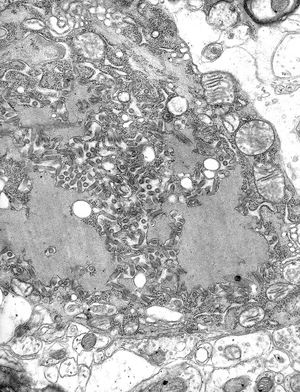

광견병바이러스는 랍도바이러스과에 속하며, 나선대칭성과 원통형의 바이러스 입자를 가지고 있고, 외피로 둘러싸여 있다. 사람에게 감염되는 바이러스는 대부분 정다면체에 가까운 형태를 보이지만, 광견병바이러스는 한쪽 끝은 뾰족하거나 둥글고 다른 한쪽은 납작하거나 오목한 총알 모양을 하고 있어 특이하다. 바이러스의 긴 부분은 대략 180nm, 짧은 부분은 대략 75nm이다.

바이러스 표면에는 당단백질로 이루어진 손잡이 모양의 스파이크가 촘촘하게 배열되어 있다. 이 스파이크는 바이러스의 평평한 부분에는 존재하지 않는다. 외피 밑에는 M단백질층이 존재하는데, 납작한 부분에서 함입되는 것으로 보인다. 바이러스의 코어는 나선형으로 배열된 리보핵단백질로 구성된다.[69]